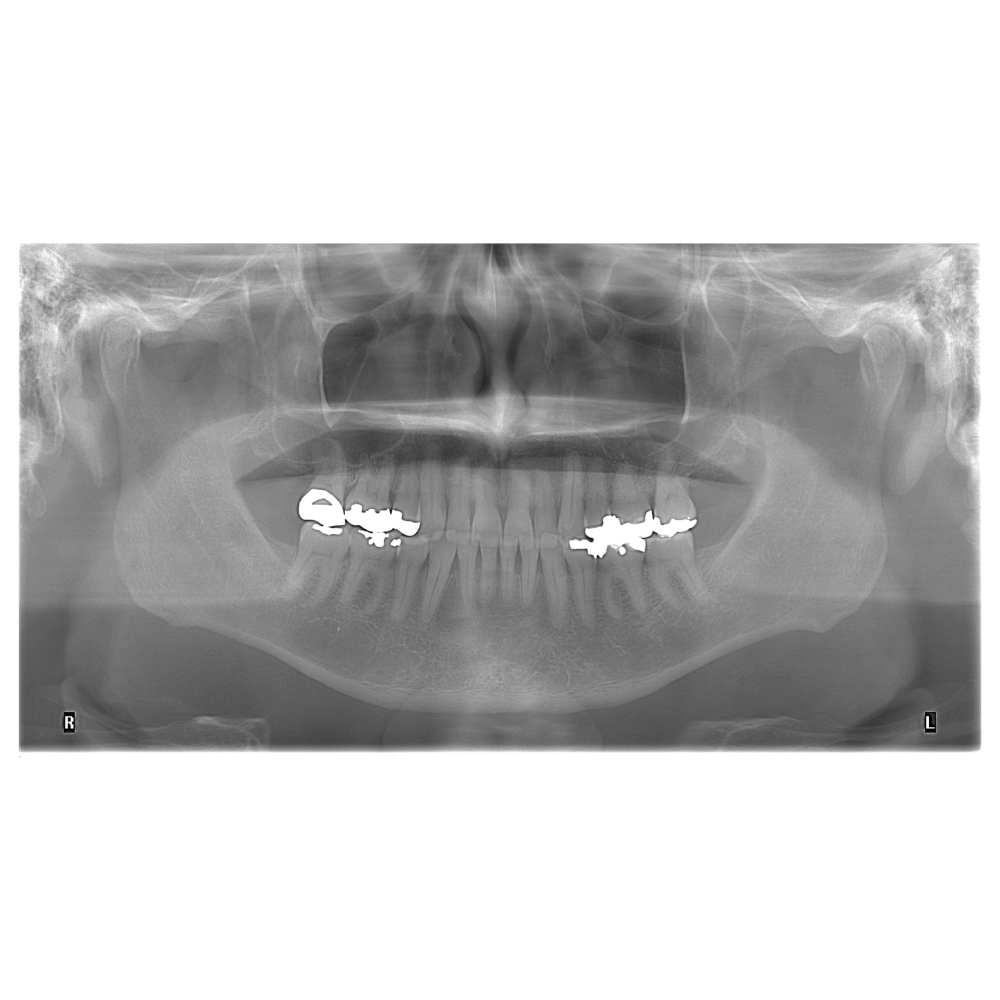

Descripción: Radiografía Panorámica (Ortopantomografía) tomada mientras el paciente muerde con la máxima intercuspidación (dientes cerrados en su posición más apretada).

Propósito: Evaluación general de dientes, mandíbulas y articulaciones temporomandibulares (ATM) en la posición de mordida habitual del paciente.